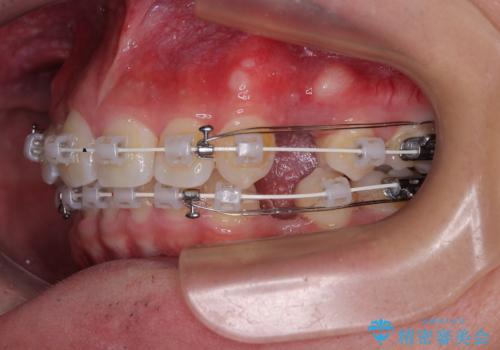

抜歯矯正で叢生と正中のずれを改善|審美装置による矯正症例

- 今回ご紹介するのは、

「全体的なデコボコ(叢生)」「上下の正中のずれ」 を主訴として来院された20代男性の患者様の症例です。

叢生が強く、歯が並ぶスペースが不足していたため、

上下左右の第一小臼歯を抜歯して、矯正治療のための適切なスペースを確保する計画としました。

上顎左側第一大臼歯に齲蝕が認められたため、矯正治療終了後に 精度の高いセラミックインレー にて修復治療を行いました。